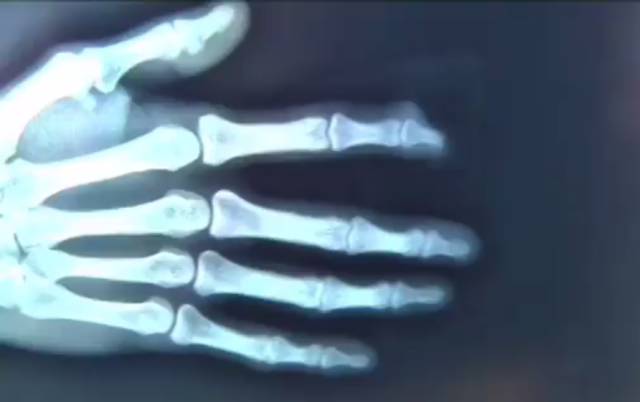

小张右手食指的第一指节,瞬间被熊吞进肚子里,顿时鲜血直流,小张惊慌失措,忍住疼痛,找到了园内的工作人员。